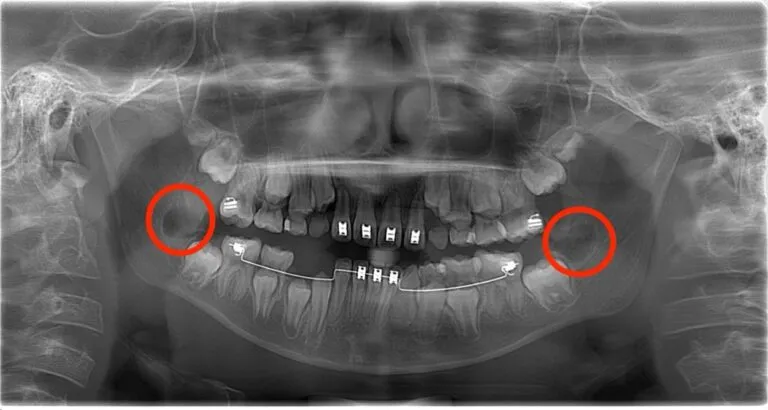

After:実際に歯胚抜歯したケース

歯根がまだ形成されていないため柔らかく、成長してからの抜歯に比べて

- 骨への負担が少ない

- 神経との距離が十分で安全

- 術後の腫れや痛みが軽い

という大きなメリットがあります。

2枚の写真を比較することで、歯胚抜歯がどのような処置か明確に理解できます。